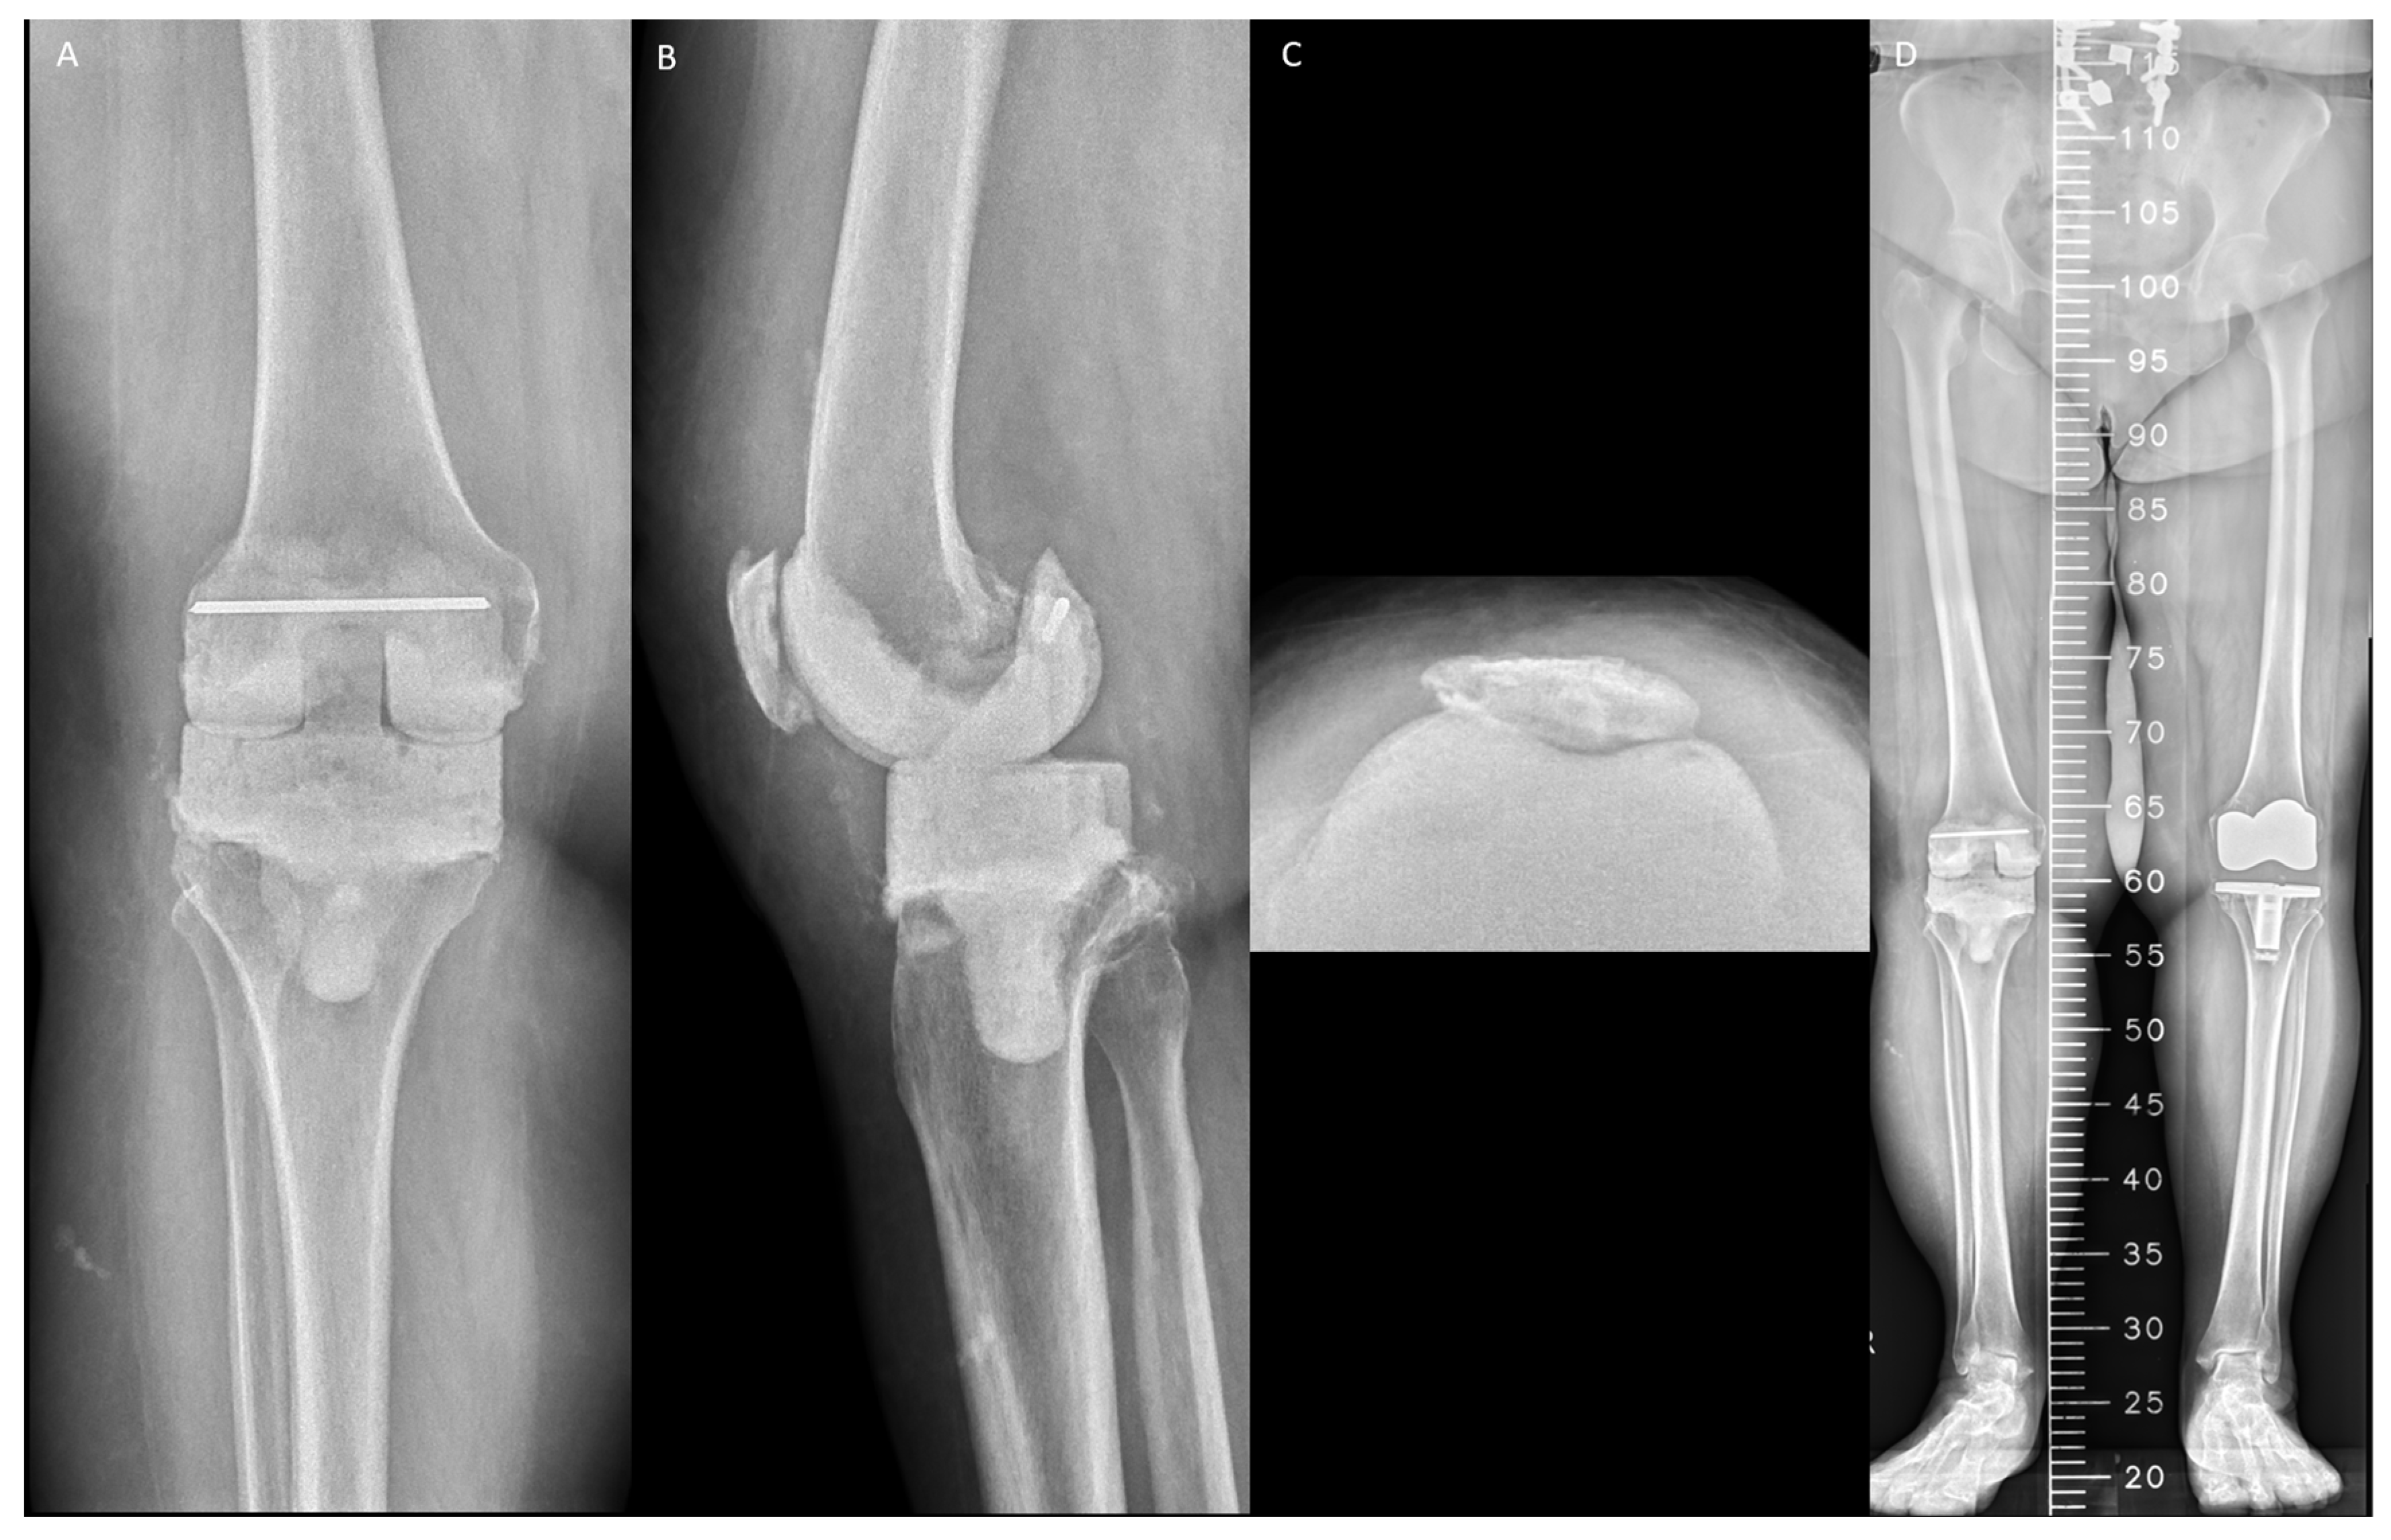

| Patient No. | Age (Years) | Sex | Radiographic Outlier | Mechanical Complication | Timing after Spacer (Weeks) | Intervention |

|---|---|---|---|---|---|---|

| HV surgeons | ||||||

| 1 | 69 | F | PTA < 87°; HKA < −10° | TS migration | 3 | Hinge knee brace |

| 2 | 64 | M | TS overhang; DFA > 98° | TS fracture | 4 | Hinge knee brace |

| 3 | 76 | M | PTA > 90°; FS notching | TS fracture | 5 | Both spacers exchange |

| 4 | 77 | F | Recurvatum deformity | Joint dislocation | 6 | Unexpected early reimplantation |